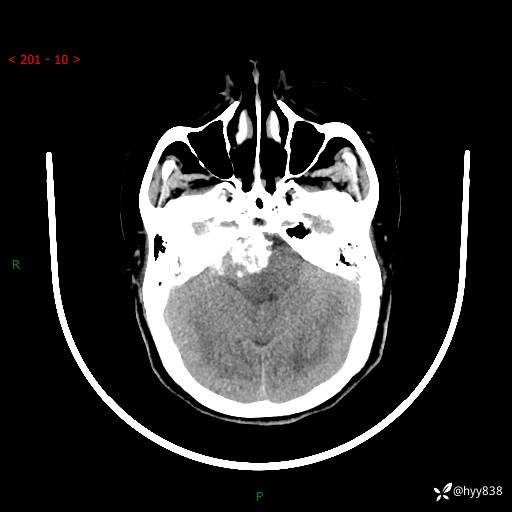

颅脑CT平扫